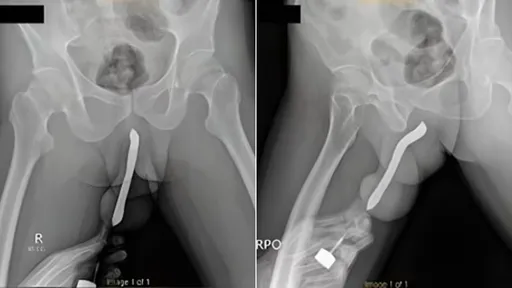

出事當晚,男子就頂著塞有牙刷的陰莖,與對象以女上男下的體位做愛,結果陰莖受傷。醫師指出,他拖了12小...

...(約5公分)。AV女優Kazumi在受訪時指出,他是因為使用女上男下的「反向女牛仔」體位做愛而釀禍。

...外力撞擊,但先前與女友性愛過程都非常激烈,長期採取女上男下性愛體位,可能是性愛過程中、角度失當而受傷...